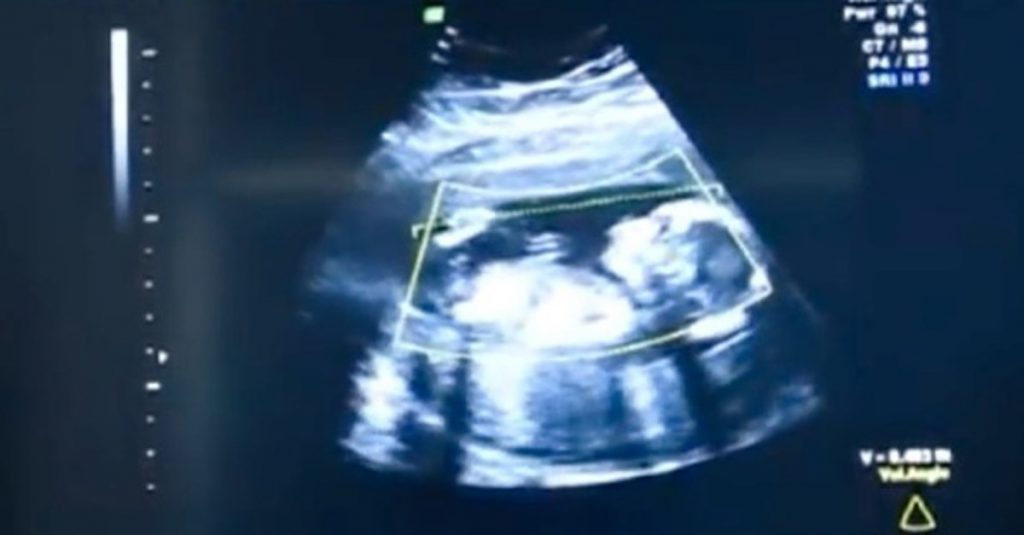

Nesse momento, os médicos precisaram fazer alguns exames nela e perceberam que seu bebê não tinha sido gerado no útero, mas em sua cavidade abdominal. Assim que perceberam a gravidade da situação, os especialistas resolveram fazer o parto para tentar salvar tanto a mãe quanto a criança. Mas, sabiam como seria muito difícil, pois nesses procedimentos, ambos podem acabar perdendo a vida.